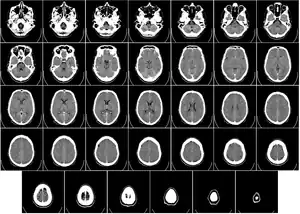

電腦斷層掃描

電腦斷層掃描是一種結合X光與電腦科技的診斷工具,利用電腦將資料組合成身體橫切面的影像,這些橫切面的影像可再進一步重組成精細的3D立體影像。電腦斷層攝影對於頭部、胸部、腹部與脊椎的問題是很好的工具,許多部位的腫瘤,例如:肺、肝、胰臟腫瘤能夠藉由這個檢查來確定位置及測量大小,對周圍組織的侵犯程度亦能提供重要的訊息。利用在創傷的病人身上,電腦斷層可以快速診斷出大腦、肝臟、脾臟、腎臟或其他體內器官的傷害情形。

電腦斷層掃描雖然可將人體器官一層層掃描進電腦來觀察,但因為電腦斷層掃描也是用X光來成像的,所以所有電腦斷層掃描影像都是灰階的黑白影像。如果由靜脈注射含碘顯影劑,血管、腎臟、肝臟等構造會被強化變得比較白,比較容易辨認。而且大多數病灶,注射顯影劑後也會較清楚,因此注射顯影劑成為電腦斷層掃描檢查的重要步驟。

電腦斷層掃描最常用的部位是頭部、耳鼻喉、胸腔、腹部、骨盆腔、脊椎、骨關節,幾乎全身各部位都可用電腦斷層掃描來檢查。而頭部外傷、骨折、脫臼不必注射顯影劑,大多數脊椎檢查亦不必注射顯影劑。電腦斷層掃描檢查本身除須暴露輻射線外,並不會有副作用,單一檢查其輻射劑量並不會對人體造成危害。所有副作用都來自對顯影劑的過敏,例如輕微過敏、噁心、皮膚癢、皮膚蕁麻疹、呼吸急促等。